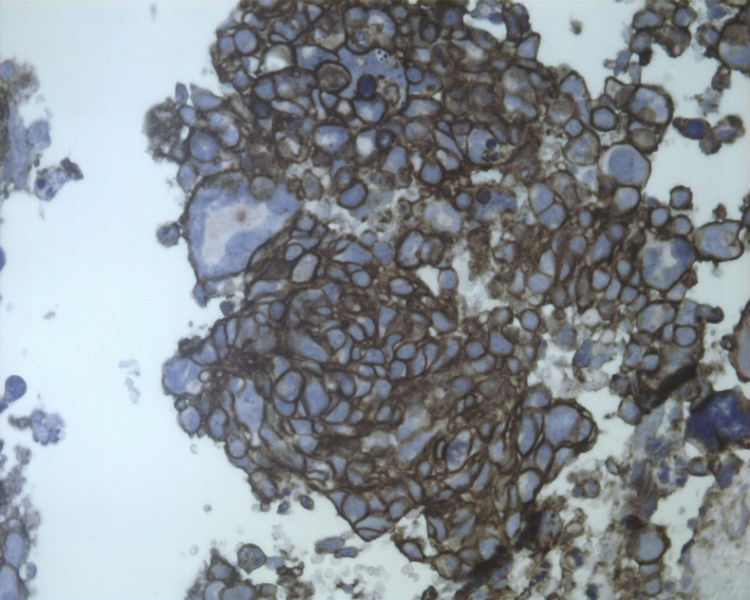

男性,50岁,右锁骨上淋巴结穿刺。

• 男性,50岁,右锁骨上淋巴结穿刺。图1

淋巴结转移性的大细胞神经内分泌癌

这是一例我以前穿刺的病例。当时涂片发现淋巴细胞的背景中散在大而非常异形的细胞。细胞没有成巢现象。

当时我考虑:

1、转移性肺的大细胞神经内分泌癌。这是我首先考虑的诊断。

2、必须要排除霍奇金淋巴瘤。不支持的地方是核仁不够明显,而且背景缺乏组织细胞、嗜酸性细胞等。

3、软组织肉瘤。

还好我当时在制作涂片的同时做了细胞腊块。现将细胞腊块的照片上传。

名称:图1 CK

描述:201106181 CK 400.jpg.jpg

名称:图2 SYN

描述:201106181 syn 400.jpg.jpg

名称:图3 CD56

描述:201106181 CD56 400.jpg.jpg

名称:图4 CGA

描述:201106181 CGA 400.jpg.jpg

结合细胞腊块及免疫组化结果,诊断了淋巴结转移性的大细胞神经内分泌癌。

细胞块的细胞成分多且有成团趋势,加上IHC支持肺来源的大细胞神经内分泌癌转移至颈部淋巴结。